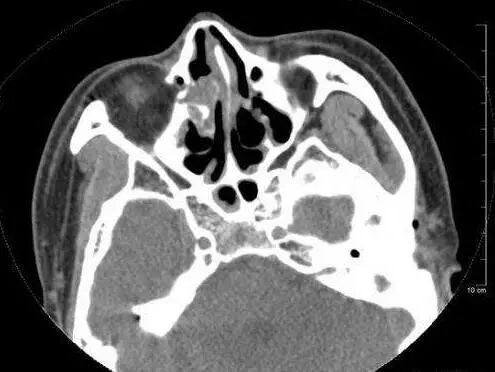

主治医生给林妹妹拍了胸片,看影像资料,非常像“肺大疱”;众所周知,肺大疱是禁止行胸腔穿刺的。在疑难杂症前,多科专家进行了圆桌会议会诊,仔细阅片,并且还追溯了患者之前在其他医院拍的胸CT,最后,专家们给出了“气胸”的诊断,并且大胆地进行了床边胸腔负压引流置管手术,患者气促明显缓解,皮氧回升,大家这时才都松了口气。

除气胸外,这位患者的胸片还呈现极为罕见的“全内脏反位”,联系到患者自小的“支气管扩张”,一个大胆的诊断浮出水面:kartagener 综合症。

这是一种罕见病,属于先天性常染色体隐性遗传病。Kartagener由支气管扩张、慢性鼻窦炎或鼻息肉、内脏反位三联症组成,主要以反复呼吸道化脓性感染、咯血为特征的支气管扩张症状及副鼻窦炎和右位心。文献报道发病率约1/68000≈1/20000。